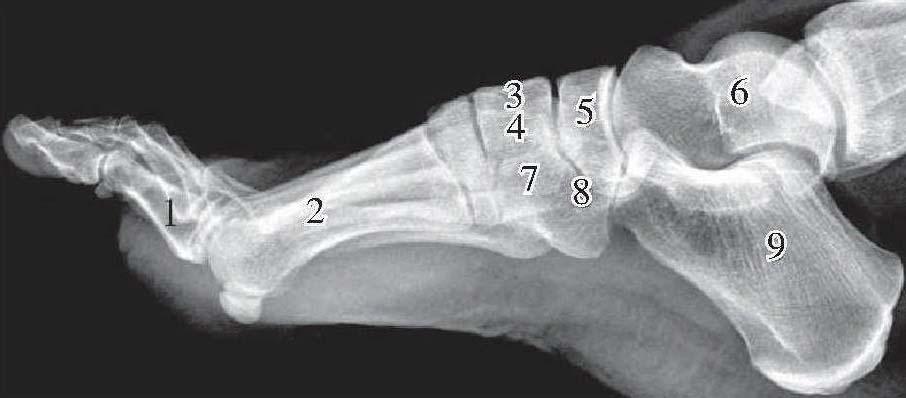

跗骨侧位

1、趾骨2、跖骨3、内侧楔骨4、中间楔骨5、足舟骨6、距骨7、外侧楔骨8、骰骨9、跟骨

距骨:位置最高,滑车向上呈圆形的隆起。滑车与胫腓两骨下端构成踝关节。车下方为距骨体,体前方稍细为颈部,再前略为膨大为距骨头。距骨体下面的关节面与跟骨上关节面构成距跟后关节。距骨头前面的关节面与足舟骨后面构成距舟关节,距骨头下面的关节面与跟骨载距突上面的关节面对应构成距跟前关节,这两关节合称为距跟舟关节。另外,距骨体的后下角呈尖形突起,称为距骨后结节。由距骨体向下还有一较大的三角形骨突影为距骨外侧突,此突越过距跟后关节间隙,以尖端与跟骨影重叠。

(2)跟骨:居距骨下方,是跗骨中最大的一块。跟骨上面有前、后两个关节面,分别与距骨构成距跟前、后关节。跟骨前面与骰骨成跟骰关节。在跟骨前上端有一向上突起为跟骨前突,此突向上与距骨头部分重叠。在跟骨前突后方,距跟后关节前方和距骨颈下方共同围成之区域为跗骨窦。在跗骨窦内或平窦之下缘有一横位的骨影为载距突,其上面平坦,与距骨颈下面对应成为距跟前关节的一部分。因它与其他结构有重叠而常不能全部显影,跟骨后下端致密粗糙,为跟结节。

(3)足舟骨:居距骨和3个楔骨之间,呈长方形,前面与3块楔骨构成关节,后面与距骨头构成关节。由足舟骨后面向后伸出三角形突起影为舟骨粗隆,它几乎与距骨头影完全重叠。

(4)骰骨:在侧位片上呈三角形,居跟骨与第4、5跖骨底之间,足舟骨和楔骨的下方。骰骨内下的尖端为骰骨粗隆。骰骨后面与跟骨构成关节,前方与第4、5跖骨底构成关节。

(5)楔骨:内侧楔骨居足舟骨和第1跖骨底之间,在侧位片上呈四边形,参与足背上缘的构成。它的前缘与第1跖骨底所构成的关节间隙在同类关节间隙中位置最前,间隙最长。中间楔骨居足舟骨与第2跖骨底之间。外侧楔骨居骰骨上方,第3跖骨底与舟骨之间,前面与第3跖骨底构成关节。